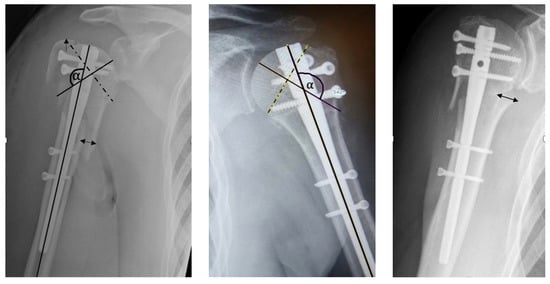

2.4. Radiographic Evaluation

| Anatomical Parameter | Anatomical | Acceptable | Malreduction |

|---|---|---|---|

| Head-Shaft-Displacement | Anatomical | <5 mm | >5 mm |

| Head-Shaft-Alignment | Normal, 120–150° | Minor varus, <120–100° | Valgus, >150°, <110° |

| Cranialization of the Greater Tuberosity | Anatomical | <5 mm | >5 mm |